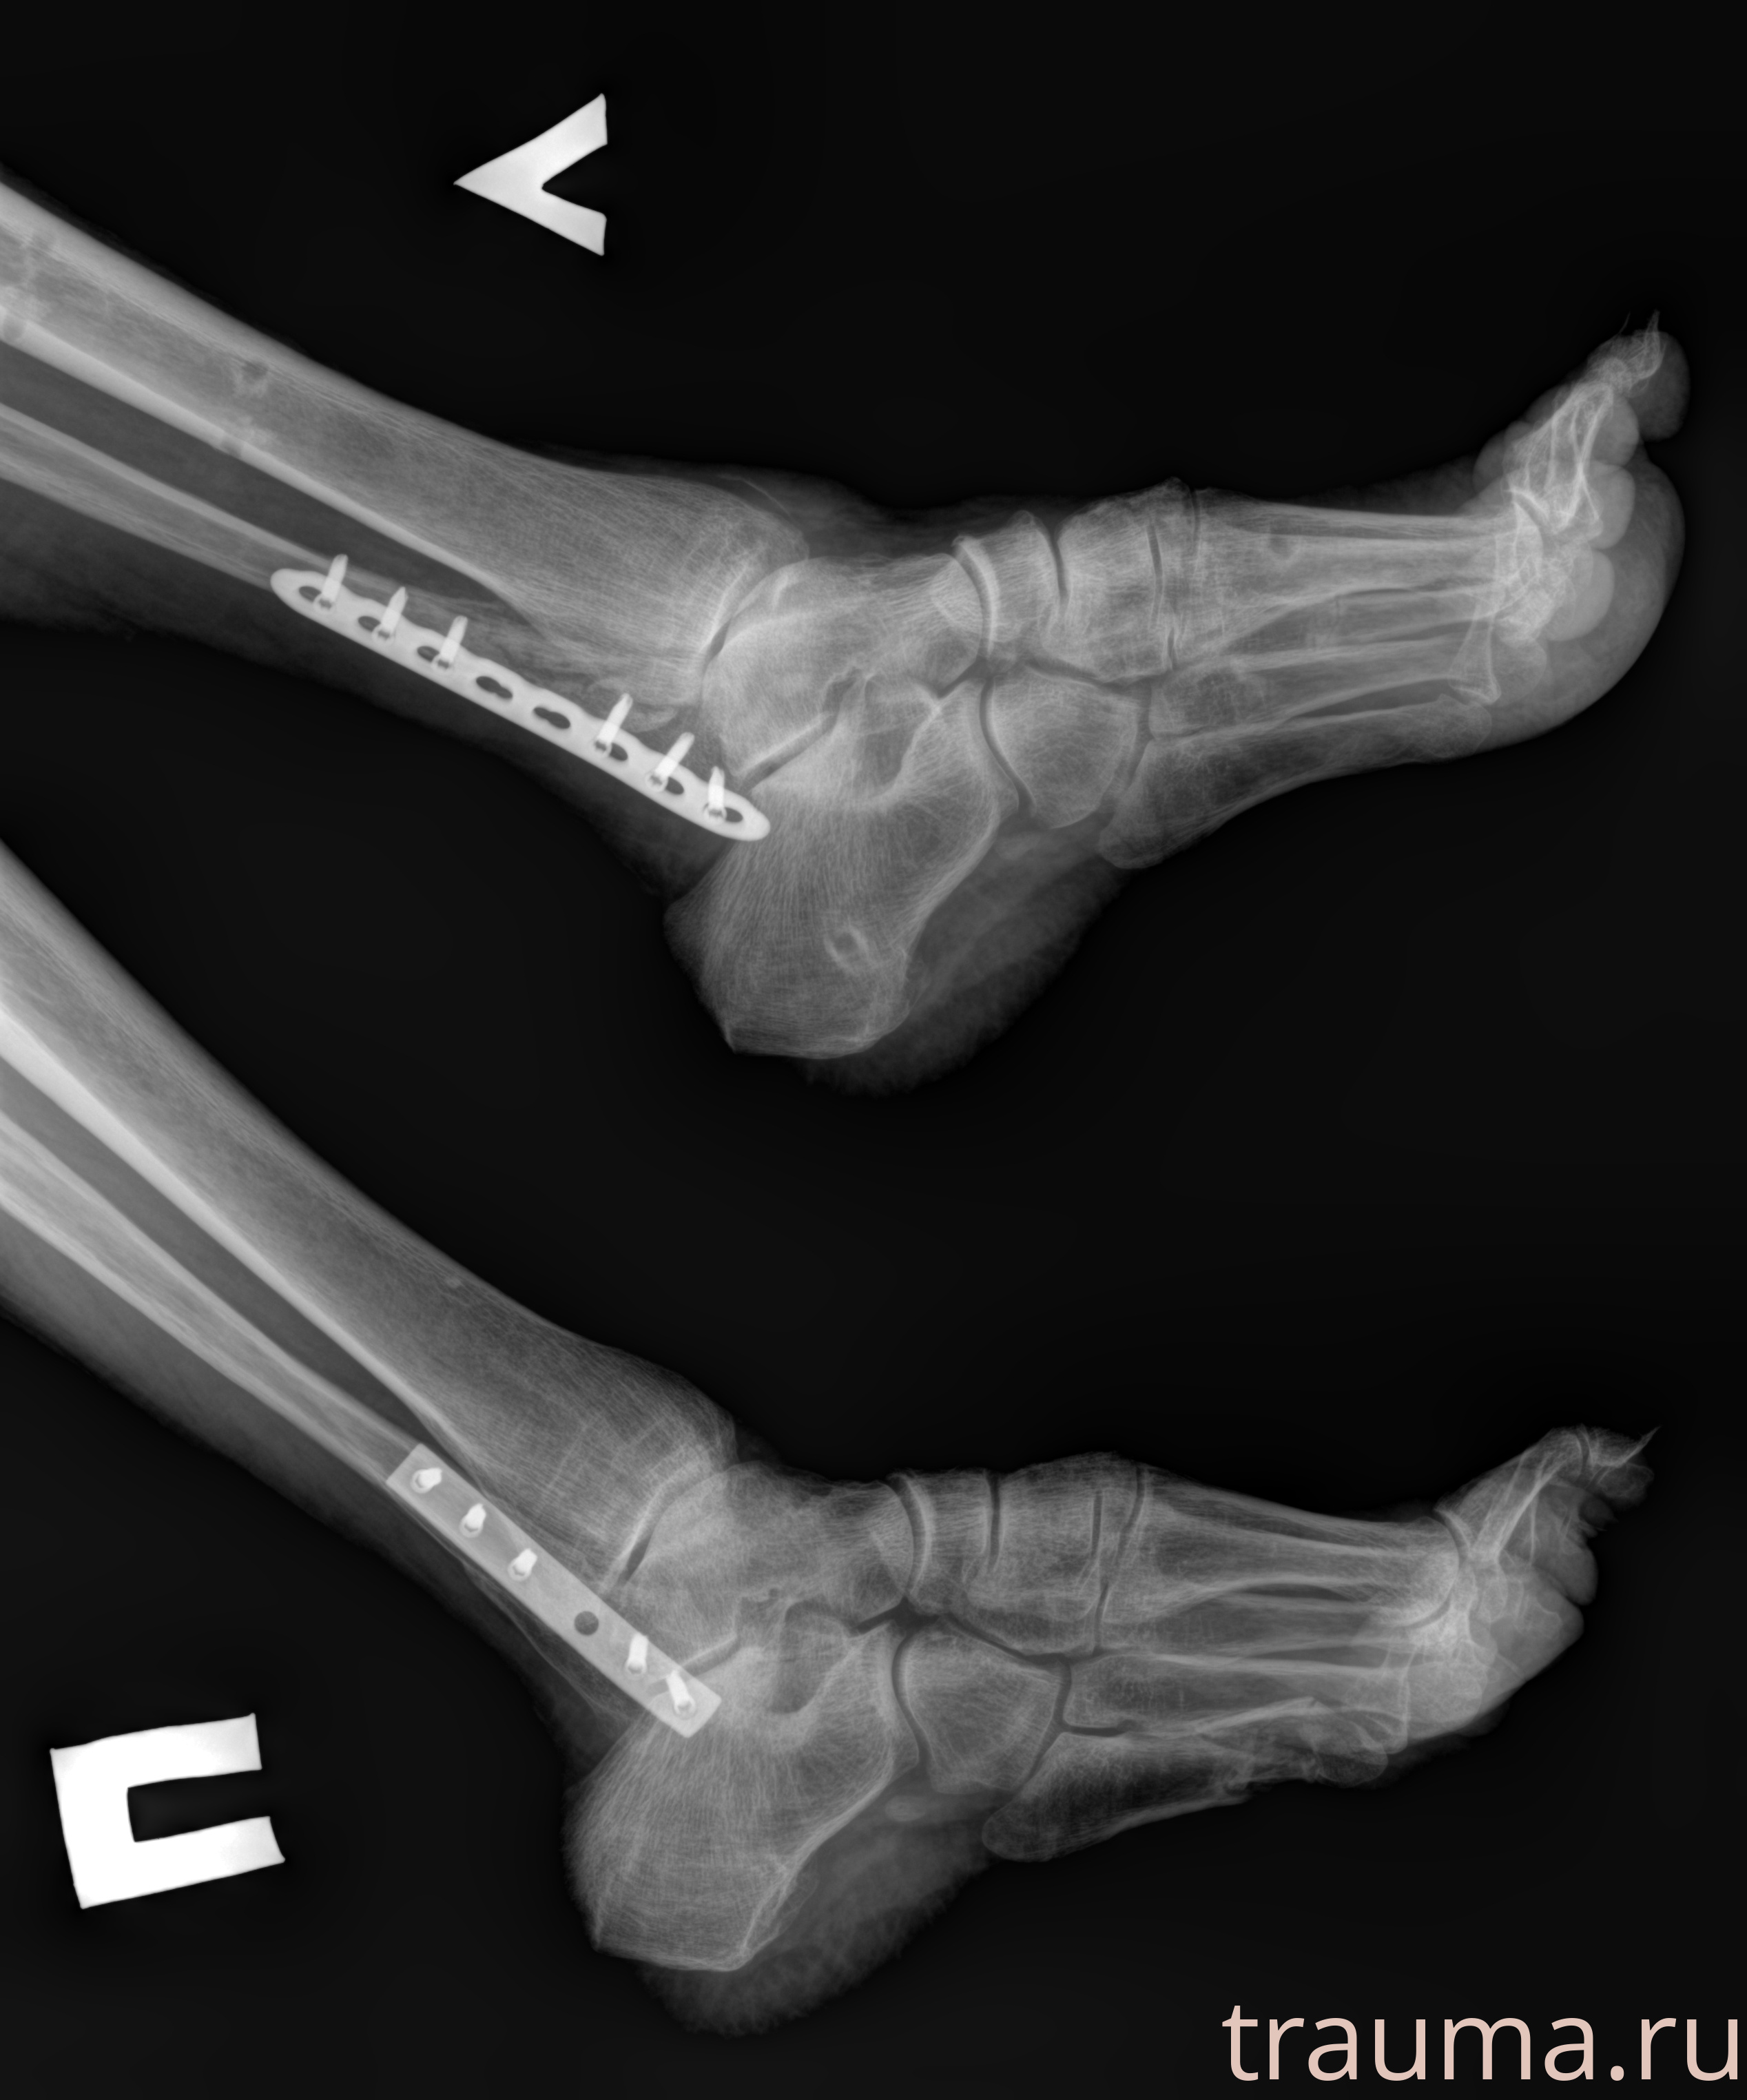

Рентгенограммы